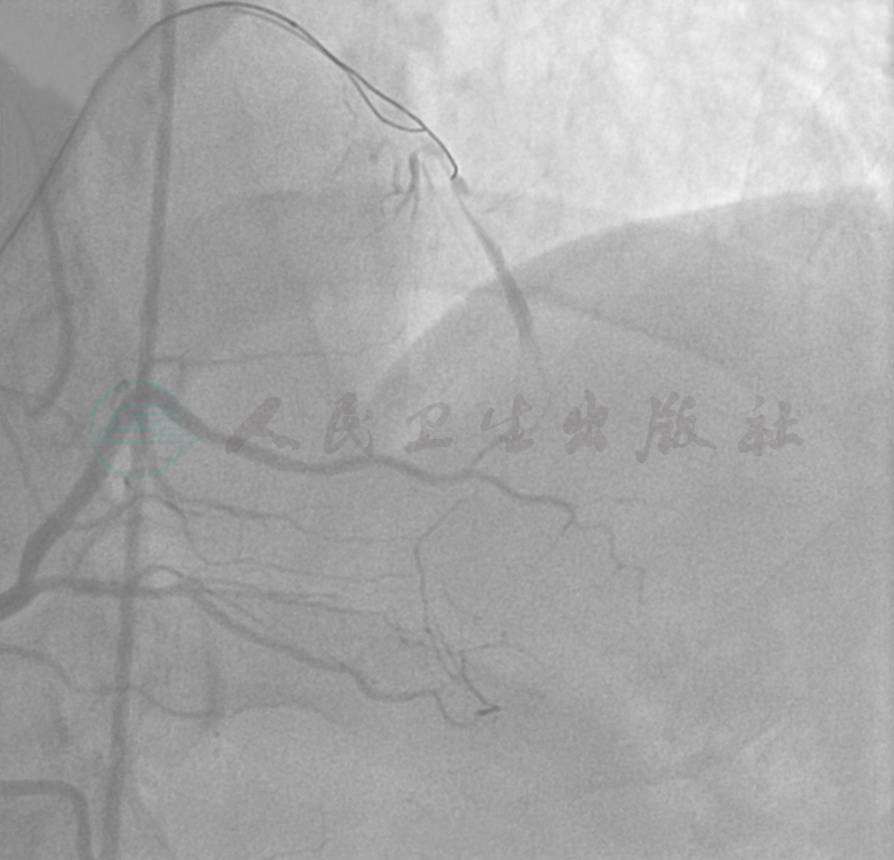

选用右桡动脉径路,6F血管鞘。造影发现:左主干可见斑块,前降支近段100%闭塞,侧支来源于右冠;右冠近段狭窄约90%(图1~图3)。

图3 右冠近段狭窄约90%,向左冠提供侧支循环